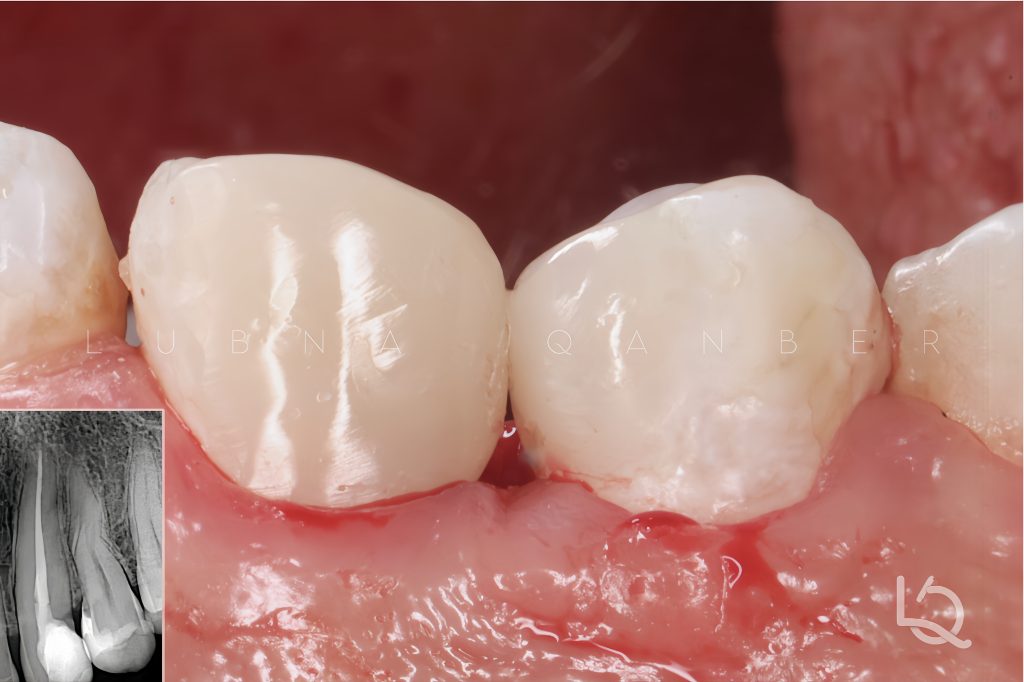

Initial Situation

A 32-year-old female patient presented to my clinic with the chief complaint of discoloration and poor shape of a composite restoration placed one year prior on the upper left canine.

Radiographic examination revealed that the canine had previously undergone root canal treatment (RCT), but the gutta-percha was underfilled by approximately 10 mm.

In addition, proximal caries were identified on both the mesial and distal surfaces of the adjacent premolars (#24, #25).